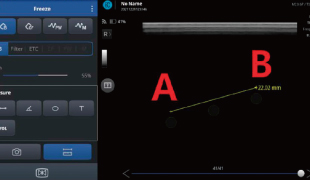

計測機能

距離(長さ)、角度、面積・外周囲、容積の計測が可能。テキスト入力も可能で、エコー画像内にメモ書きすることで、情報の引継ぎも簡単です。